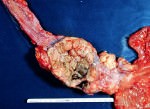

Стадии

I стадия — Опухоль располагается в одной анатомической области (либо в глотке, либо в гортани), не сопровождается изъязвлением и метастазами

II стадия - Опухоль распространяется на соседние органы, определяются единичные метастазы в лимфатические узлы

III стадия — Крупная опухоль, прорастающая соседние органы и ткани, с изъязвлением, многочисленными местными метастазами

IV стадия — Появляются метастазы в отдалённые органы